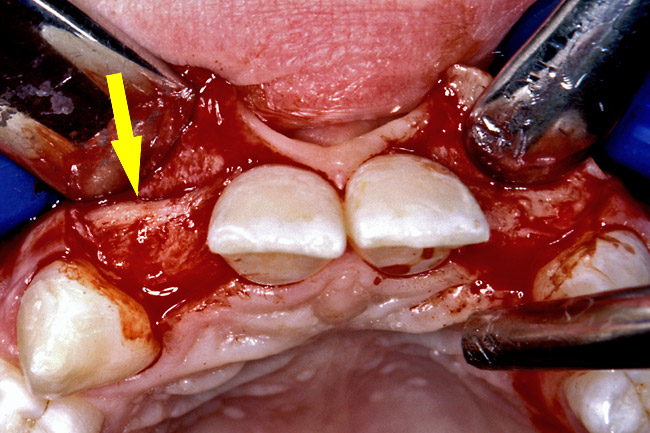

Before the day of surgery, the patient was seen by the orthodontist for the removal of the orthodontic brackets. The patient still was not pleased with the position of the two centrals, and it was determined that this would be addressed after implant placement (Figure 13A). The anatomical variations of the crestal tissue and lack of interdental papilla can be appreciated in the close-up views of the right and left sites (Figure 13B and 13C). There were no surprises on the day of surgery as all of the decisions were made during the planning phase, before the scalpel ever touched the patient. The occlusal view of the CT 3D model revealed the wider alveolar ridge on the right side and thinner crest on the left side (Figure 14A). This was confirmed when the full thickness mucoperiosteal flaps were elevated, and the underyling bone revealed (Figure 14B). The tooth-borne templates were designed to facilitate the drills and drilling sequence specific to the diameters of the predetermined implants (Figure 15A). Each template contained an embedded 5-mm long stainless steel tube, which was approximately 0.2-mm wider than each drill (just wide enough to allow for the drills to rotate freely). Once positioned over the natural teeth, the template was secure and offered precision accuracy in transferring the implant locations from the original software-designed plan, allowing the potential for internal and external irrigation (Figure 15B). The 3.7-mm diameter Tapered Screw-Vent implant drilling sequence requires three drills: pilot, intermediate, and final sizing. Thus, three separate templates were fabricated to a.commodate these sizes. The templates were removed easily and replaced with the next sequential size in less time than it takes to change the drill on the surgical handpiece. After the osteotomies had been.completed, the implants were delivered to the site (Figure 16A and Figure 16B). For this internal hex connection implant, the author r.commends that the flat of the antirotational hex be positioned to the facial for proper orientation of the restorative.components (Figure 17A). Preprepared margins were created from a milled titanium fixture mount transfer post, which was delivered to the implant as support for an immediate transitional restoration. The facial “dot” helped confirm the orientation of the abutment to the facially positioned flat side of the internal hex connection (Figure 17B). Before cementation of the transitional acrylic restorations, a closed-tray, fixture-level impression was made, and a soft-tissue model fabricated.

Figure 14a  The information gained from (A) the 3D model was confirmed when (B) the flaps were elevated.

Figure 14a

Figure 14b  The information gained from (A) the 3D model was confirmed when (B) the flaps were elevated.

Figure 14b